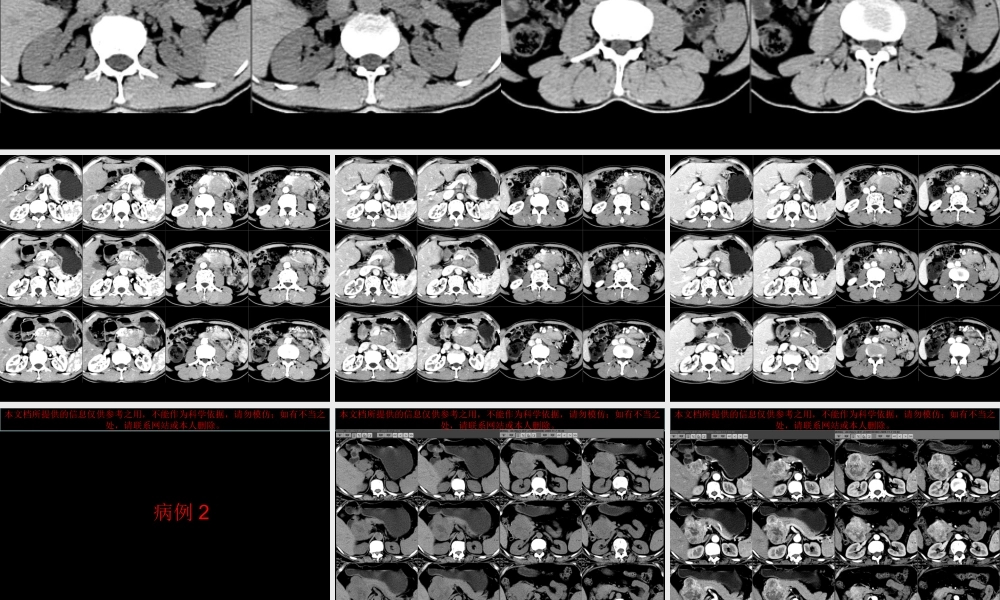

本文档所提供的信息仅供参考之用,不能作为科学依据,请勿模仿;如有不当之处,请联系网站或本人删除。本文档所提供的信息仅供参考之用,不能作为科学依据,请勿模仿;如有不当之处,请联系网站或本人删除。本文档所提供的信息仅供参考之用,不能作为科学依据,请勿模仿;如有不当之处,请联系网站或本人删除。本文档所提供的信息仅供参考之用,不能作为科学依据,请勿模仿;如有不当之处,请联系网站或本人删除。本文档所提供的信息仅供参考之用,不能作为科学依据,请勿模仿;如有不当之处,请联系网站或本人删除。病例 2本文档所提供的信息仅供参考之用,不能作为科学依据,请勿模仿;如有不当之处,请联系网站或本人删除。本文档所提供的信息仅供参考之用,不能作为科学依据,请勿模仿;如有不当之处,请联系网站或本人删除。本文档所提供的信息仅供参考之用,不能作为科学依据,请勿模仿;如有不当之处,请联系网站或本人删除。本文档所提供的信息仅供参考之用,不能作为科学依据,请勿模仿;如有不当之处,请联系网站或本人删除。病例 3本文档所提供的信息仅供参考之用,不能作为科学依据,请勿模仿;如有不当之处,请联系网站或本人删除。本文档所提供的信息仅供参考之用,不能作为科学依据,请勿模仿;如有不当之处,请联系网站或本人删除。本文档所提供的信息仅供参考之用,不能作为科学依据,请勿模仿;如有不当之处,请联系网站或本人删除。本文档所提供的信息仅供参考之用,不能作为科学依据,请勿模仿;如有不当之处,请联系网站或本人删除。Castleman 病CT 表现小讲座 福建医科大学附属第一医院影像科孙辉红( sunhvhong@sina.com )本文档所提供的信息仅供参考之用,不能作为科学依据,请勿模仿;如有不当之处,请联系网站或本人删除。病例 1•男, 58 岁,反复左上腹胀痛半年余。肿瘤标志物正常•*1 甲胎蛋白 (AFP) 1.580 0-13.6 ng/ml 电化学发光法 •*2 癌胚抗原 (CEA) 2.1 0-5.2( 吸烟者 :0-6.5) ng/ml 电化学发光法 •3 糖类抗原 125(CA125) 5.760 0-35 U/ml 电化学发光法 •4 糖类抗原 15-3(CA15-3) 10.230 0-25 U/ml 电化学发光法 •5 糖类抗原 19-9(CA19-9) 1.420 0-34 U/ml 电化学发光法 •6 糖类抗原 72-4(CA72-4) •淀粉酶 (AMYL) >35632 bg 32-641 U/L 干化学 强生 本文档所提供的信息仅供参考之用,不能作为科学依据,请勿模仿;如有不当之处,请...